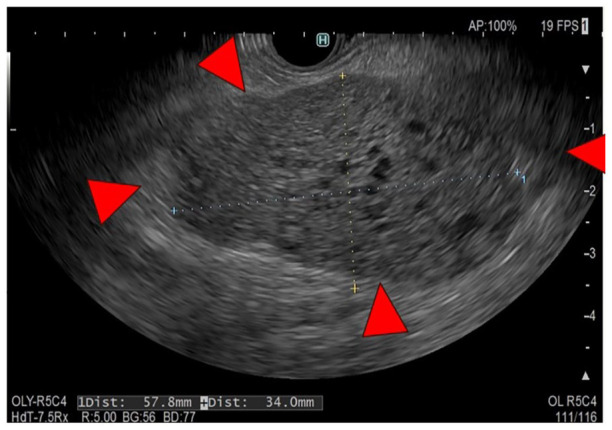

Neuroendocrine cells are distributed throughout the body's organs, though neuroendocrine neoplasms are primarily documented in the gastrointestinal tract and pancreas, with rare occurrences elsewhere. Herein, we report a case of primary neuroendocrine tumor of the omentum (omental NET) that was incidentally detected as an omental mass during preoperative screening for colorectal cancer. The patient, a 66-year-old woman, with abdominal pain and decreased oral intake, leading to a diagnosis of obstructive colorectal cancer with a large, 55 mm, mass around the gastropyloric region, which was discontinuous with the gastrointestinal tract. After the placement of a colonic stent at the site of the ascending colon cancer to decompress the colon, a laparoscopic right hemicolectomy was performed, simultaneously excising the mass. Postoperative pathology revealed a neuroendocrine tumor (NET). Subsequent examinations detected no other lesions of suspected primary disease and postoperative somatostatin scintigraphy found no other lesions, establishing a diagnosis of omental NET. The rarity of omental NETs is attributable to the absence of neuroendocrine cells in the omentum. Moreover, solid tumors originating primarily from the omentum are very rare, making preoperative diagnosis difficult; therefore, postoperative pathology should be utilized. We presented a very rare case of omental NET, previously reported only once in the literature, and believe that complete resection with minimal invasiveness should be performed for treatment of this malignancy. In addition, we emphasize the need for continued patient follow-up.

Abstract Image